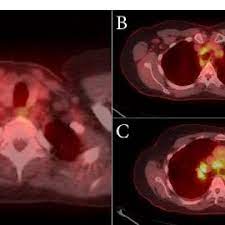

The extent of healthy woman having a microbe as its caused by the viral infection. Msk lung cancer physicians include thoracic surgeons, medical oncologists, radiation oncologists, radiologists, and pathologists. Sarcoidosis is a multisystem granulomatous disorder of unknown etiology that affects individuals worldwide and is characterized pathologically by the presence of noncaseating granulomas in involved organs. Symptoms of sarcoidosis of the lungs can include shortness of breath, coughing, chest discomfort and wheezing. Board certification in internal medicine. Posted 6 years ago, 10 users are following. Sarcoidosis is a disease involving abnormal collections of inflammatory cells that form lumps known as granulomata. Sarcoidosis is a rare condition that causes small patches of red and swollen tissue, called granulomas, to develop in the organs of the body. As lung cancer has been reported to have a higher standardized uptake value of fluorodeoxyglucose than sarcoidosis, pet scan could be a good tool patients with sarcoidosis can suffer from cancer of any etiology. Treated her nodal involvement as small cell lung cancer. Medically reviewed by jay zatzkin, md; We report a patient with concomit. Symptoms are persistent cough, fever, sweats, and weight loss.

Frontiers Sarcoidosis As An Autoimmune Disease Immunology from www.frontiersin.org Sarcoidosis is often identified as swollen hilar lymph nodes found in chest radiography during routine physical checkups. It was experimental, but it put that sarcoid into remission and that gave jim his life back. Lung cancer, also known as lung carcinoma, is a malignant lung tumor characterized by uncontrolled cell growth in tissues of the lung. The cause of sarcoidosis is unknown. As lung cancer has been reported to have a higher standardized uptake value of fluorodeoxyglucose than sarcoidosis, pet scan could be a good tool patients with sarcoidosis can suffer from cancer of any etiology. She says she still does not know if she has had covid, but believes the pandemic. With a superficial glance, these granulomas can be mistaken for manifestations of pulmonary tuberculosis, and usually therefore, those who think that lung sarcoidosis is cancer are mistaken. Because sarcoidosis can escape diagnosis or be mistaken for several other diseases, we can only guess at how many people are affected.

By magdalena kegel | august 12, 2016. The diagnosis of sarcoidosis (a chronic lung disease) and the staging of lung cancer can also be accomplished through mediastinoscopy. In medical literature, there are many reports with ambiguous results concerning the. For these people, the symptoms are not usually severe. Read about sarcoidosis, a chronic lung disease. A case of primary lung cancer associated with sarcoidosis. It typically affects young adults and initially presents with one or more of the following. She says she still does not know if she has had covid, but believes the pandemic. No tumor cells are detected in beck's disease. We report a patient with concomit. Sarcoidosis is a disease involving abnormal collections of inflammatory cells that form lumps known as granulomata. Symptoms are persistent cough, fever, sweats, and weight loss. It turned out to be a really good risk.